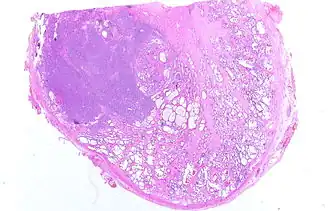

Локализация опухоли

В 60—70 % случаев опухоль при раке простаты возникает в её периферической зоне. В центральной зоне опухоль появляется лишь в 5—10 % случаев, а остальные случаи приходятся на переходную зону[13].

Патофизиология

Большинство опухолей простаты начинаются в периферической зоне – самой внешней части простаты. Когда клетки начинают расти бесконтрольно, они образуют небольшой комок нерегулируемых клеток, называемый простатической интраэпителиальной неоплазией (ПИН).[27] Некоторые ПИН продолжают расти, образуя слои ткани, которые прекращают экспрессировать гены, общие для их исходного расположения в ткани – p63 , цитокератин 5 и цитокератин 14 – и вместо этого начинают экспрессировать гены, типичные для клеток во внутренней оболочке протока поджелудочной железы – цитокератин 8 и цитокератин 18. Эти многослойные ПИН также часто сверхэкспрессируют ген AMACR, который связан с прогрессированием рака простаты.[28]